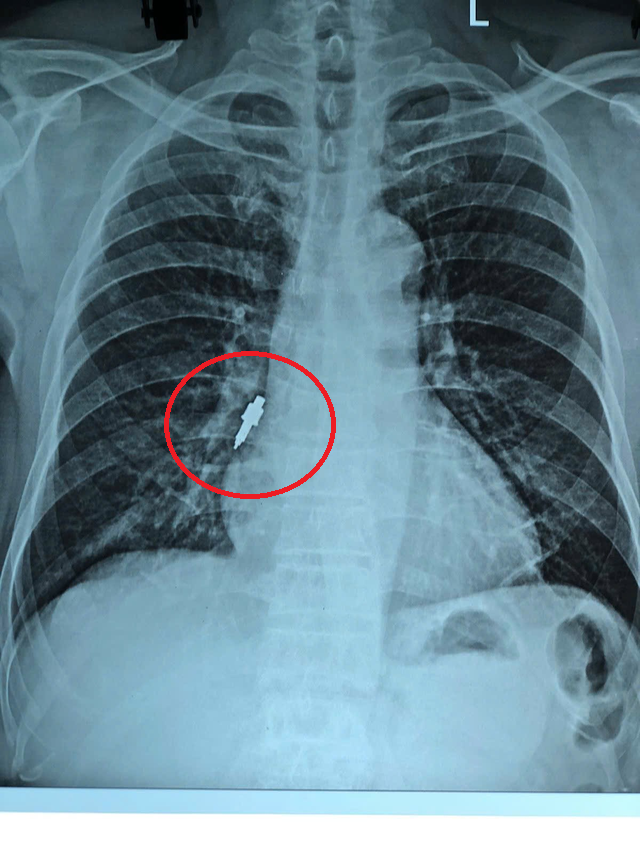

Sau thủ thuật, người đàn ông bắt đầu ho nhẹ, không cải thiện theo thời gian. Những ngày gần đây, cơn ho trở nên dữ dội và kéo dài, buộc gia đình đưa ông đi kiểm tra. Kết quả chụp X-quang cho thấy một dị vật lớn trong phế quản phải.

Tại đây, các bác sĩ tiến hành nội soi phế quản khẩn. Dị vật được xác định là một mảnh dụng cụ bằng inox, bề mặt trơn, đường kính khoảng 1 cm, dài 2,5 cm, mắc sâu trong phế quản phải.